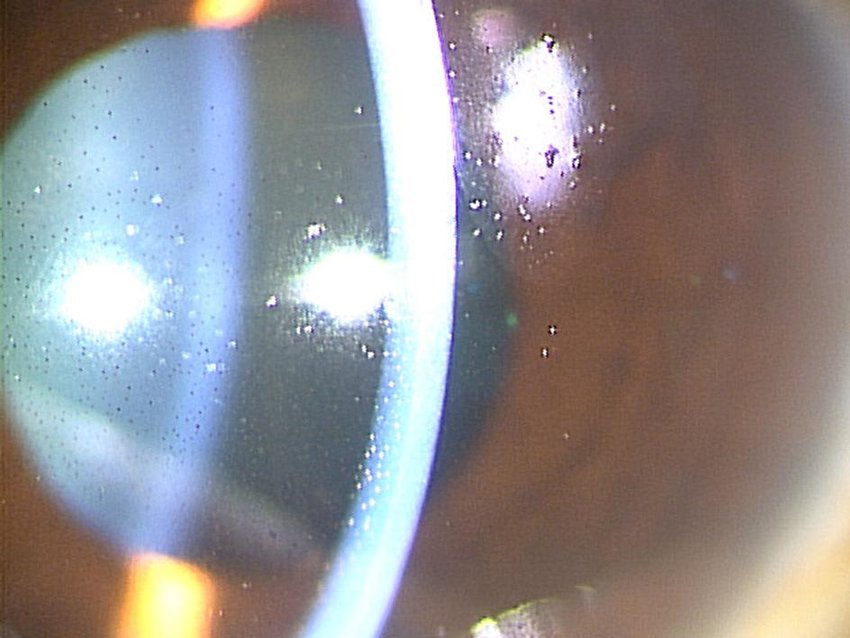

<중심시력소실, Snuff out sydrome, Wipe out syndrome>

중심시야만 조금 남아 있던 환자의 시야가

녹내장 수술이후 오히려 남아있던 중심시야가 없어지면서,

시력을 완전히 잃게되는 경우를 Snuff out syndrome 혹은 Wipe out syndrome 이라고 합니다.

문헌에 따라 보고는 다른데 0% ~ 7.7% 까지 다양하게 보고되어 있으며,

- 고령,

- 수술전 시야손상이 주시점을 침범한 경우

- 수술후 심한 저안압에 빠지는 경우

이러한 경우등에서 수술이후 유일하게 남아있던 중심 시력이 완전히 소실되는 경우가 보고되어 있습니다.

하지만, 수술전 시야가 남아있는 정도가 얼마나 남았는지에 따라서 수술의 금기가 되지는 않습니다.